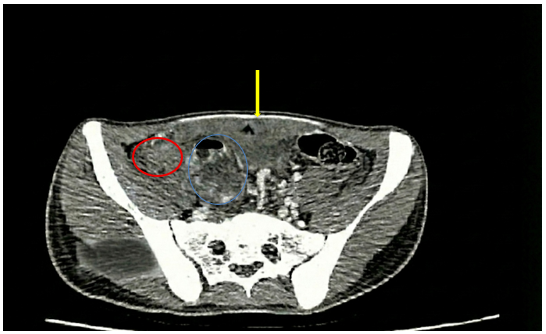

-       CLVT ổ bụng(29/11/2025):

Hình ảnh ổ dịch – khí vùng tiểu khung kích thước 22x15mm (vùng khoanh tròn màu xanh dương), thâm nhiễm mỡ rộng (vùng khoanh tròn màu đỏ), dày phúc mạc kèm dịch vùng tiểu khung dày 12mm (vùng mũi tên màu vàng)